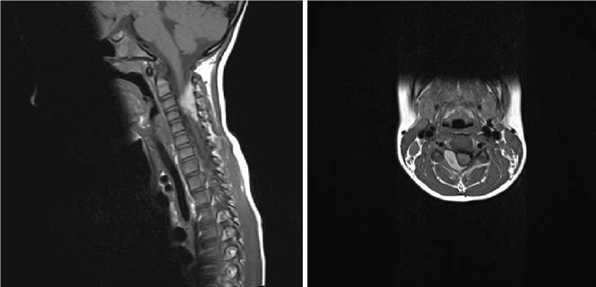

Figure 1: Preoperative MRI scan.

A 6-year old girl was admitted to Pediatric Neurosurgical Unit presenting with severe neck pain, stiffness and decrease in neck movement. She did not have any weakness in upper or lower limbs. Her symptoms started ten days earlier when she received a punch in the neck while she was playing with other children in her kindergarten. Her mother took her to the chiropractic but the symptoms sustained. After the hospitalization hematological profile was analysed and the results were within normal limits (platelet count 333x109/L, prothrombin time 0.73, international normalized ratio 1.15, partial thromboplastin time 29 seconds, fibrinogen 2.1g/L). The MRI scan of the cervical spine showed epidural hematoma with spinal cord compression extending from C2 to C4 vertebral levels (Figure 1). Emergency operation was indicated. Surgery was performed in prone position. Midline vertical skin incision extending from C2 to C5 levels was made and right-sided C4 hemilaminectomy and evacuation of the underlying epidural hematoma were performed. No masses or vascular anomalies were detected during the operation. Skin was suttured and the patient was postoperatively transferred to the Pediatric Neurosurgical Unit. Histopathological diagnosis was: hematoma. She was released from the hospital on the fifth postoperative day. At the moment of the release she was neurologically intact with recuperated neck movement and no neck pain. The MRI scan that was performed 8 weeks after the surgery demonstrated normal postoperative findings with good morphology of the spinal canal and its structures and without signs of the residual epidural collection (Figure 2). During the follow up in the outpatient clinic she was asymptomatic and neurologically intact.